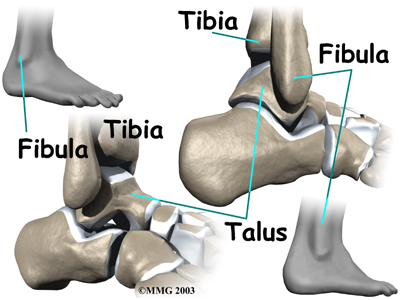

A syndesmosis is a joint where the rough edges of two bones are held together by thick connective ligaments. The connection of the lower leg bones, the tibia and fibula, is a syndesmosis. The tibia is the main bone of the lower leg. The fibula is the small, thin bone that runs down the outer edge of the tibia.

Only a few joints in the body are syndesmosis joints. In addition to the ankle syndesmosis (the connection of the tibia and fibula), syndesmosis joints are also located in the lower spine, where the top of the triangular-shaped sacrum bone fits between the pelvis bones.

Most joints in the body are synovial joints. Synovial joints are enclosed by a ligament capsule and contain a fluid, called synovium, that lubricates the joint. The ankle syndesmosis sits next to the ankle synovial joint, where the tibia meets the talus bone.

The syndesmosis ligaments hold the bottom ends of the tibia and fibula in place. This arrangement forms the upper surface of the ankle joint. The ankle joint is a hinge joint. The hinge is formed where the tibia and fibula sit above the talus bone. This connection is called a mortise and tenon, a stable connection that woodworkers and craftsmen routinely use to create strong and stable constructions.